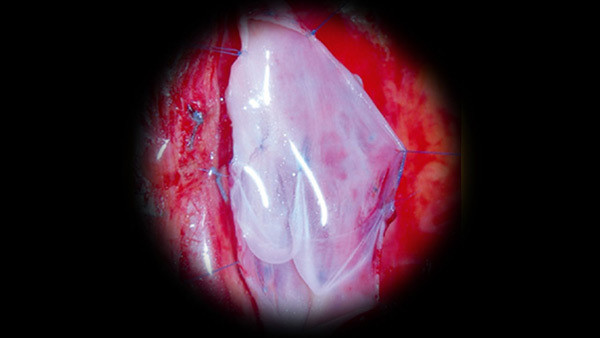

专家指出,这扇神奇的门其实就是我们人体的静脉瓣膜。它主要分布在我们的四肢,其中下肢的瓣膜尤其重要,所以对于下肢的慢性静脉疾病,这扇门的作用更为重要。人体的静脉瓣膜是和小腿肌肉一起协同作用使血液回流到心脏的,这期间,静脉瓣膜究竟是如何工作的呢?专家现场用多组道具生动形象的讲解了它的工作过程。同时,根据病程的发展,静脉瓣膜功能不全被分为0-6期。这7个时期都有各自的显著特征,每一期都有比较明显的症状,而这些早期症状同时也就是我们的早发现信号。其中的0期就是我们最容易忽视的时期。这个时期的特点:“有症状无体征”,代表的就是当我们出现某些症状时,身体上不会出现明显变化。这个时期时,如果我们的下肢出现:沉重感、酸胀感、晨轻暮重等症状,也就是提示我们静脉瓣膜已经出现问题,一定要赶紧注意了,不要等到发展成像夏老先生那种最严重的第六期时后悔莫及。由于在老年人中的高发病率,主持人在现场调查中就找到一位阿姨,经过专家的现场诊断,她就是患有第二期的静脉曲张。